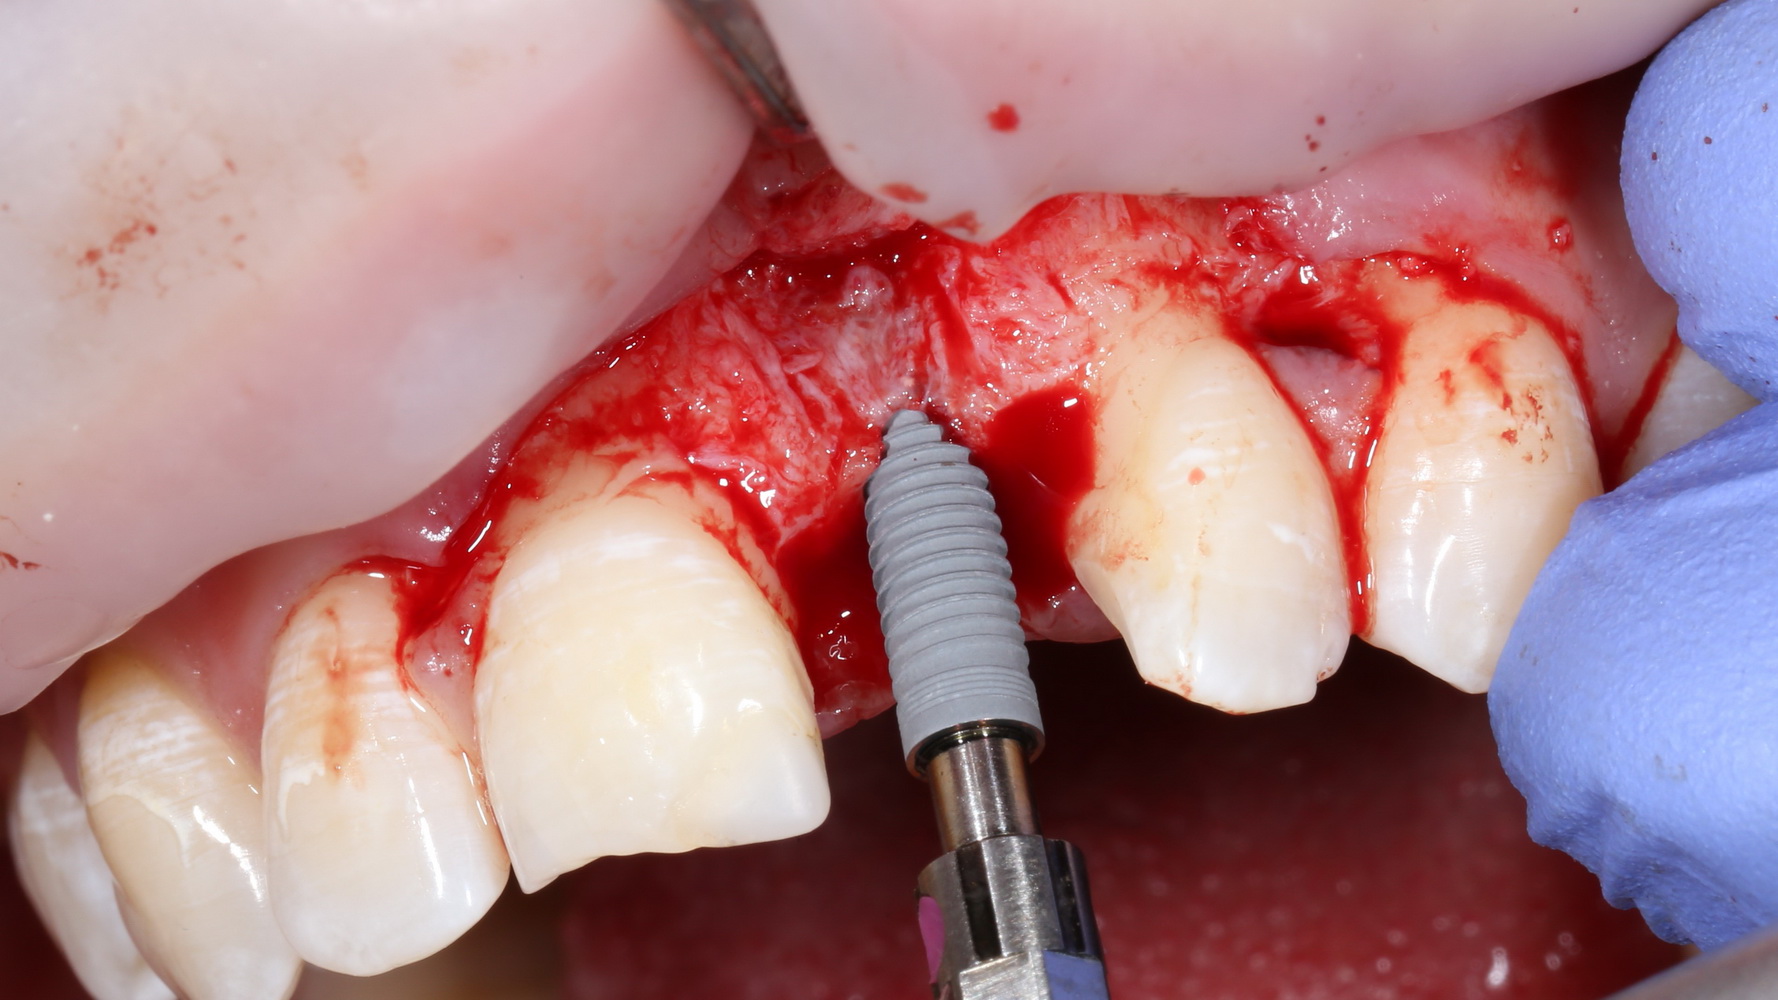

Теперь можно готовить лунки под импланты:

A09A5459 (2)

В данном случае я планирую установить импланты Nobel Replace Conical Connection:

A09A5461 (2) A09A5462 (2)